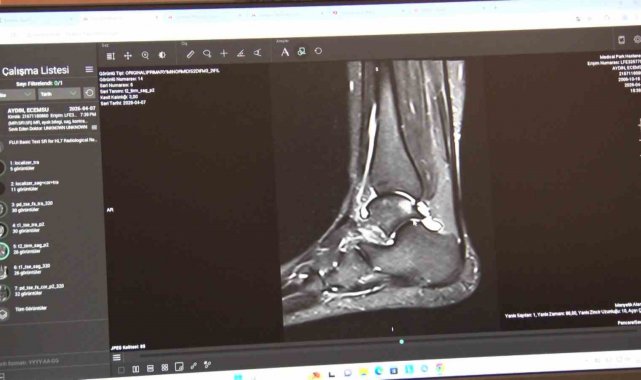

Klinik pratikte en sık karşılaştıkları spor yaralanmalarına da değinen Serarslan, özellikle halı sahada yapılan futbolun sakatlık riskini artırdığını belirterek, "Bizim klinik pratiğimizde en sık karşılaştığımız sakatlıkları birkaç gruba ayırabiliriz. Birincisi ani travmayla gelişen akut yaralanmalar, ikincisi ise zamanla tekrarlayan zorlanmalara bağlı oluşan kronik problemler. En çok karşılaştığımız akut travmalar arasında diz yaralanmaları, ön çapraz bağ yaralanmaları, menisküs yaralanmaları, kas travmaları, kas yırtıkları, omuz çıkıkları, omuz bağ ve kas yırtıkları ile özellikle aşil tendon yaralanmaları yer alıyor. Türkiye'de halı sahada futbol çok yaygın ama bu zemin sakatlık açısından da çok riskli bir alan oluşturuyor" ifadelerini kullandı.